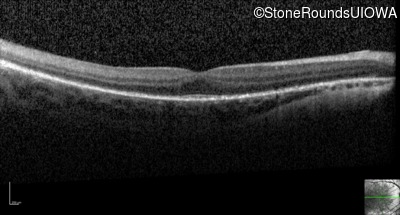

Optical Coherence Tomography - Right - 20/50 +1 sc

Exemplar / OCT Stack